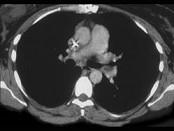

女,51岁,心脏手术后,突感胸痛,结合CT图像,最可能的诊断是 ( )A、肺癌B、肺不张C、支气管扩张D、肺水肿E、肺栓塞

问题 女,51岁,心脏手术后,突感胸痛,结合CT图像,最可能的诊断是 ( )

选项 A、肺癌 B、肺不张 C、支气管扩张 D、肺水肿 E、肺栓塞

答案 E